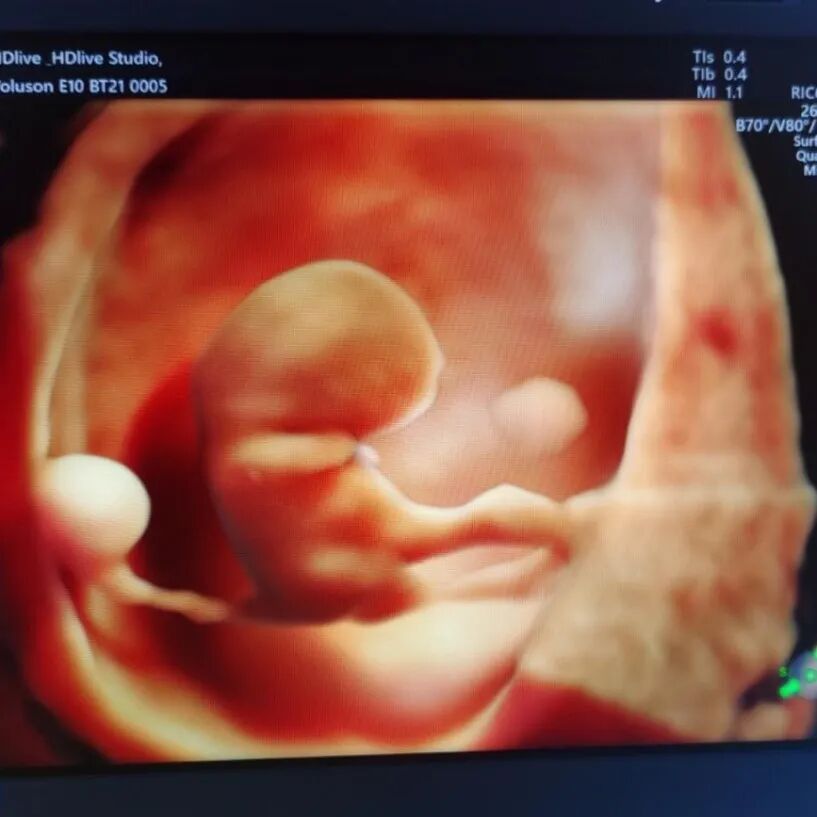

二、高清画质,成像效果惊人

相较普通四维彩超,E10的高清画质堪比IMAX电影大片!

过去的四维彩超能看到宝宝吐舌头、吃手指,但常常看到胎宝宝就像个“小泥人”,只能看看大致轮廓;E10四维彩超,可以实现您与宝宝的超高清“隔空对视”,直接观察他们的一举一动、乖巧秀容,包括:皱眉、微笑、打哈欠、吸吮等,提前享受将为人父人母的喜悦。